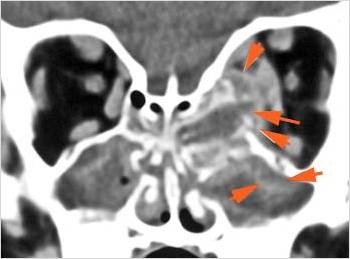

The orbital apex and the superior and inferior orbital fissures are infiltrated. [Yes/No]

There is evidence of thrombus, thrombophlebitis or other occlusive or inflammatory process of the cavernous sinus. [Yes/No]